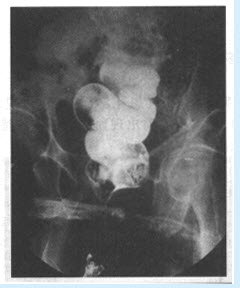

患者,男,25岁。近几年出现吞咽梗阻感,偶出现胸骨后疼痛。行食管吞钡检查如图。

A:病因是食管神经肌肉运动功能障碍,下段食管括约肌呈失弛缓状态而导致食管张力减退、蠕动消失及食管扩张

E:典型的X线表现为食管狭窄并其上段极度扩张